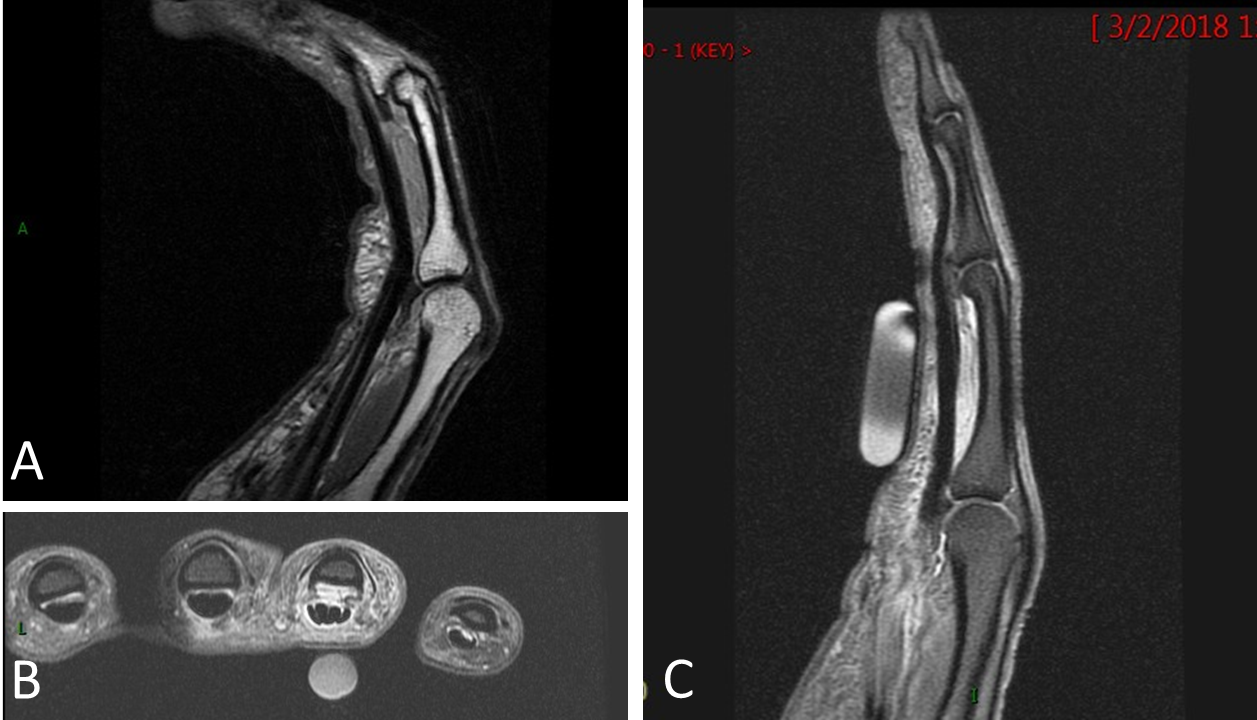

From radiopaedia.org

Finger A2 pulley injury Image Finger Pulley Injury Surgery Invasive repair is now seen as a last resort and even then, usually only considered if you’ve ruptured multiple pulleys at the same time. How to rehab a pulley injury. The good news is that not all injuries need surgery. Pt jeff’s comprehensive rehabilitation program for finger pulley injuries. However, this will largely depend on the severity of your injury.. Finger Pulley Injury Surgery.